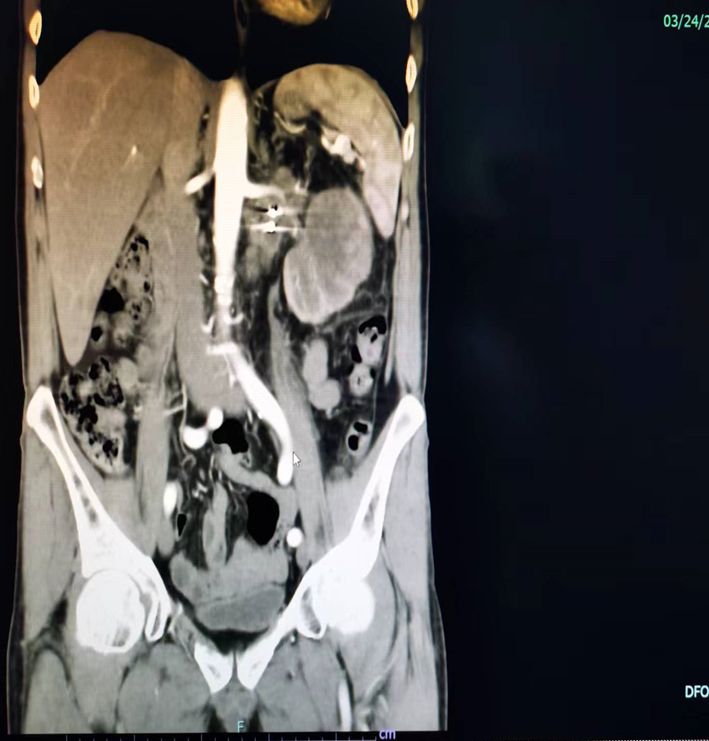

1患者,男性,55歲2、2023年1月因“間斷左下腹脹痛1月余”于當(dāng)?shù)厥兄行尼t(yī)院就診3磁共振檢查提示左腎中極占位性病變,考慮腫瘤性病變可能性大并散在淋巴結(jié)轉(zhuǎn)移4腎穿刺活檢送武大人民病理會診:(腎)高級別浸潤性尿路上皮癌浸潤腎實(shí)質(zhì),伴大量壞死5于2023.2.14-2.22日行第1周期吉西他濱+順鉑GP化療6于2023.2.20日行CT引導(dǎo)下左腎周淋巴結(jié)轉(zhuǎn)移瘤碘125粒子植入術(shù)7于2023.3.8-2023.3.15行第2周期吉西他濱+順鉑GP方案化療8既往史:有高血壓、冠心病、腦梗塞病史,2020年于外院行冠脈動脈支架植入術(shù),口服藥物單硝酸異山梨酯緩釋片、美達(dá)信、阿司匹林腸溶片等于2023年3月因不能耐受化療副作用到專家門診找我,以“腎盂癌、冠心病、腦梗、高血壓”收治入院完善檢查后行一體位腹腔鏡下腎盂癌根治+腎蒂淋巴結(jié)清掃手術(shù),術(shù)后痊愈出院

對于腎盂癌,以前是都是做開放手術(shù),上腹部一個大切口,下腹部一個大切口?;颊邉?chuàng)傷很大,術(shù)后恢復(fù)也比較慢?;颊吒共績蓚€大的切口,觸目驚心!現(xiàn)在微創(chuàng)技術(shù)進(jìn)步了,對于有經(jīng)驗(yàn)豐富的外科醫(yī)生,完全可以采用腹腔鏡的手術(shù)來完成。首先,在上腹部打三個小孔,完成腎切除和輸尿管上段的游離,然后下腹部再打一個小孔,完成輸尿管下段和膀胱入口的袖套狀切除。最后只需要一個小切口,將切除的標(biāo)本取出來。昨天手術(shù)的這位患者,因?yàn)榉磸?fù)肉眼血尿就診,雖然CT上考慮是右腎腫瘤,但是根據(jù)我的經(jīng)驗(yàn),實(shí)際上應(yīng)該是右側(cè)腎盂腫瘤,所以按照原則做了腹腔鏡右側(cè)腎盂癌根治術(shù)?;颊哂覀?cè)腎上腺有個小的腫物,懷疑是轉(zhuǎn)移,也同時做了切除?;颊咝g(shù)前CT報(bào)告患者術(shù)前CT影像把切除的標(biāo)本取出來之后,明顯感覺腫物質(zhì)地比較硬,具體還要等最終的病理結(jié)果。肉眼血尿是泌尿系統(tǒng)腫瘤的典型癥狀,一旦出現(xiàn)這種情況,一定要及時就診。早期手術(shù)效果比較好。對于分期比較晚和分級比較高的腫瘤,術(shù)后一般建議結(jié)合輔助治療,減少腫瘤的復(fù)發(fā)和轉(zhuǎn)移。